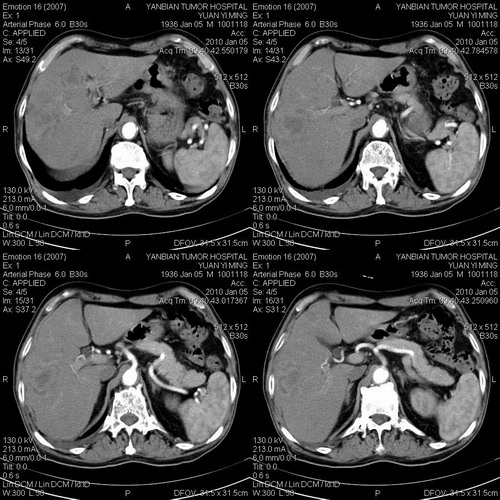

标题: CT24024:男,74岁。体检超声发现肝内多发占位性病变四天。 [打印本页]

标题: CT24024:男,74岁。体检超声发现肝内多发占位性病变四天。

肝癌肝内转移,胃壁增厚,胃癌不能排除

建议查afp。考虑多发结节型肝癌。

1)考虑肝脏恶性肿瘤(转移瘤?)。2)肝外胆管轻度扩张。3)左肾小囊肿。

考虑转移瘤。